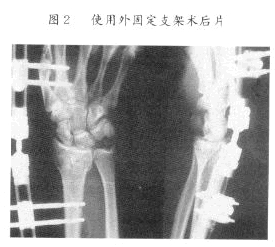

2、開放復位、內固定

適用於手法復位失敗者或復位後固定困難者;上肢多處骨折 , 骨間膜破裂者;開放性骨折 , 傷後時間不長、污染較輕者;骨不連或畸形癒合、功能受限者。

2開放復位內固定

適用於手法復位失敗者或復位後固定困難者;上肢多處骨折骨間膜破裂者;開放性骨折傷後時間不長污染較輕者;骨不連或畸形癒合功能受限者。